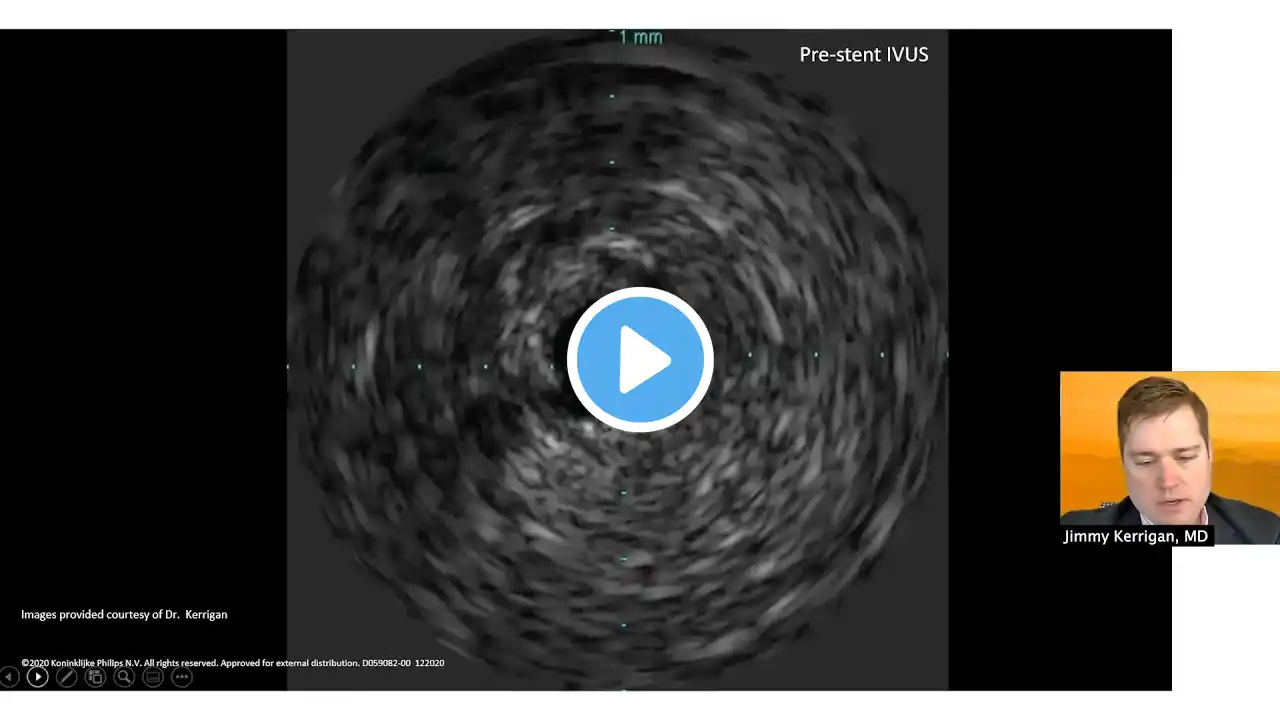

Park and colleagues reviewed data as well as clinical and histologic studies of DES which demonstrate evidence of continuous neointimal growth during long-term follow-up.